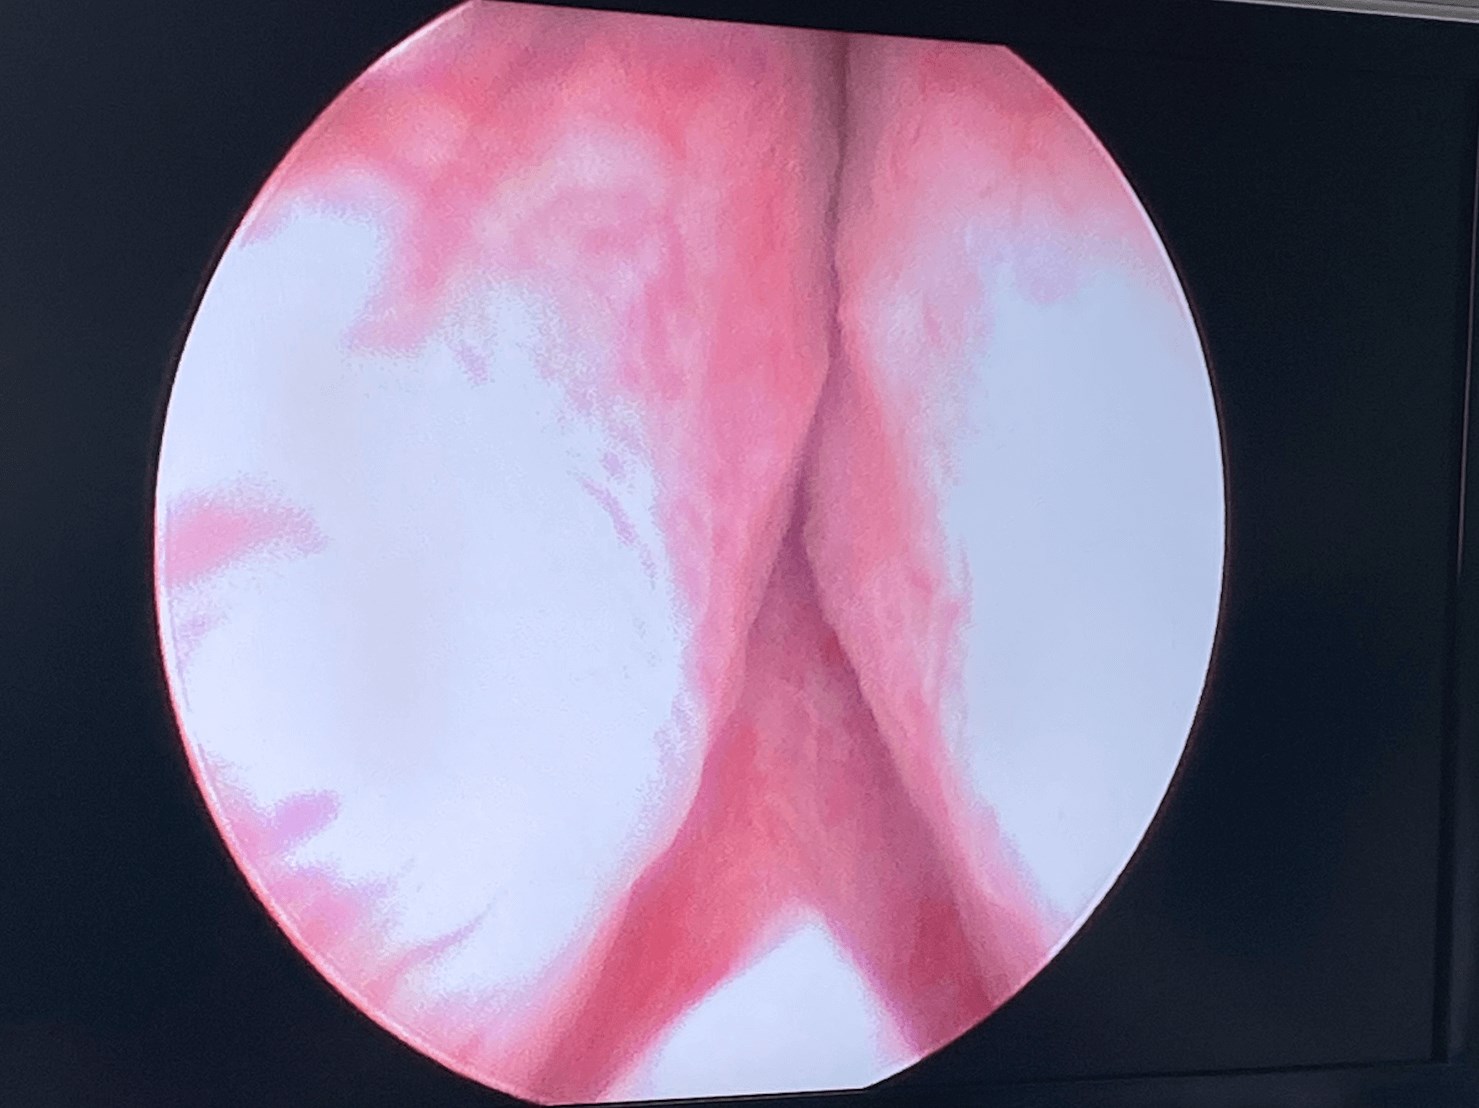

Patient had complications with ejaculating before Urolift

Procedure